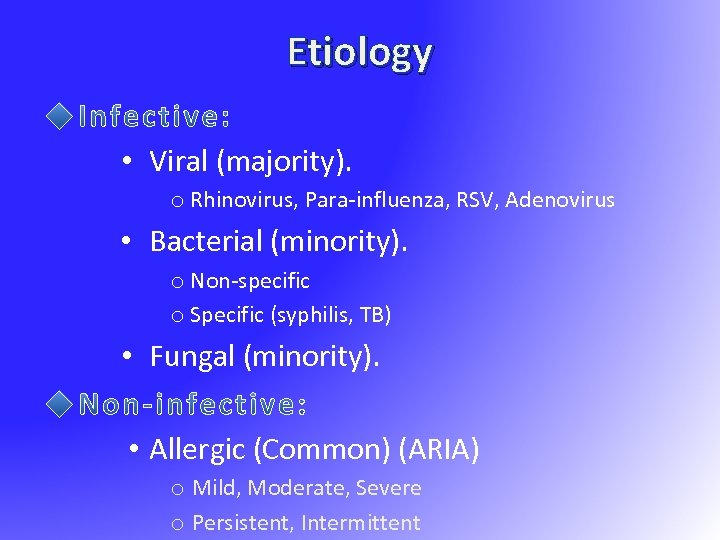

Etiology • Viral (majority). o Rhinovirus, Para-influenza, RSV, Adenovirus • Bacterial (minority). o Non-specific o Specific (syphilis, TB) • Fungal (minority). • Allergic (Common) (ARIA) o Mild, Moderate, Severe o Persistent, Intermittent

Etiology • Viral (majority). o Rhinovirus, Para-influenza, RSV, Adenovirus • Bacterial (minority). o Non-specific o Specific (syphilis, TB) • Fungal (minority). • Allergic (Common) (ARIA) o Mild, Moderate, Severe o Persistent, Intermittent